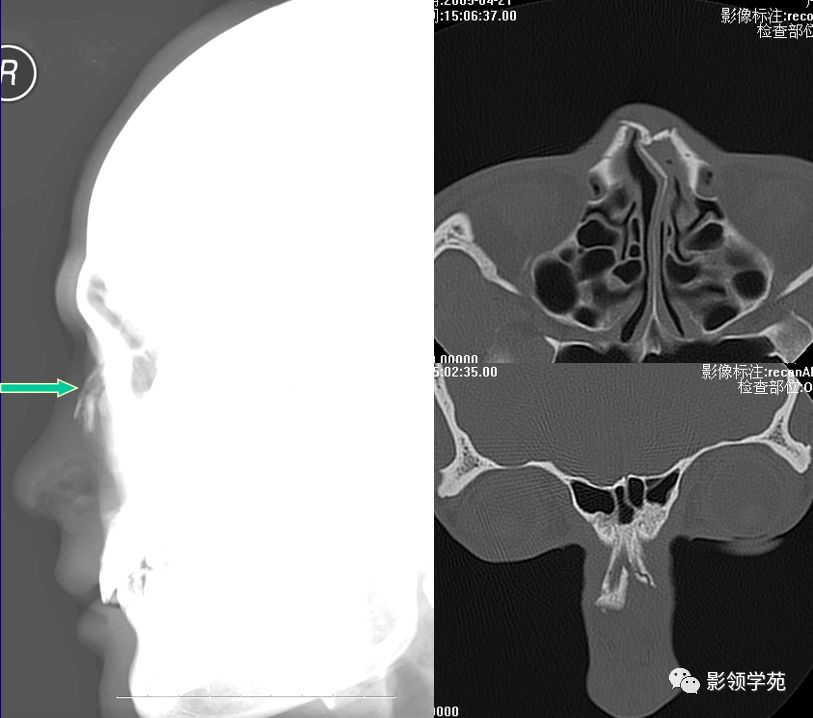

X线平片:侧位

HRCT

- 横断面:听眶下线

- 冠状面:鼻骨长轴平行线

- 层厚:1~2mm

鼻骨正常侧位

鼻骨横断面HRCT

鼻骨冠状面HRCT

线性骨折 粉碎骨折

右侧鼻骨线形骨折

鼻骨线形骨折

右侧鼻骨骨折

双侧鼻骨骨折

鼻中隔骨折